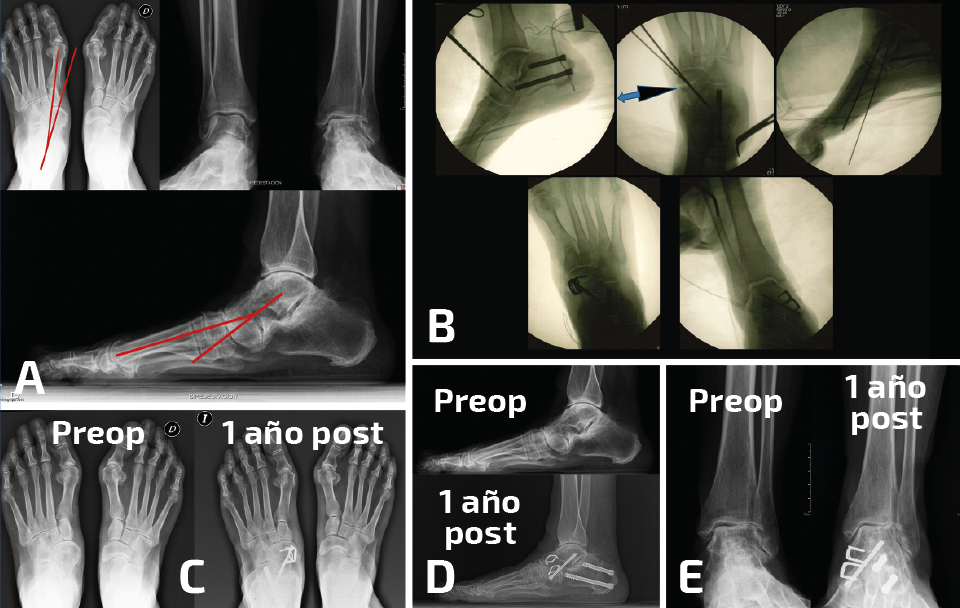

- Demasiado valgo: algunas dobles/triples artrodesis tarsianas pueden acabar fijadas con un excesivo valgo. Las consecuencias clínicas serían las opuestas al escenario descrito anteriormente y los signos radiológicos serían también los contrarios. Lo que no varía es el planteamiento de corrección para llegar al CORA de la deformidad y poder realizar osteotomías correctoras. La modificación de la alineación suele conllevar también una mejoría importante en el dolor del tobillo (Figura 4).

Figura 4. Paciente con consolidación viciosa de una doble artrodesis tarsiana que muestra excesivo valgo y un tobillo con una artropatía asimétrica y muy doloroso. A: el estudio radiológico muestra la deformidad en valgo y la transmisión de ese valgo a la tibiotalar; B: en las imágenes de radioscopia intraoperatoria se aprecia la realización de una osteotomía varizante de calcáneo y de una osteotomía de cierre talonavicular con una cuña de base medial y plantar; C: radiografías de ambos pies en carga en proyección dorsoplantar que muestran las diferencias en la alineación al año de la cirugía; D: misma situación en proyección lateral; E: radiografías de ambos tobillos en carga en proyección anteroposterior que muestran las diferencias en la asimetría al año de la cirugía. La paciente se encontraba asintomática de su dolor tibiotalar.